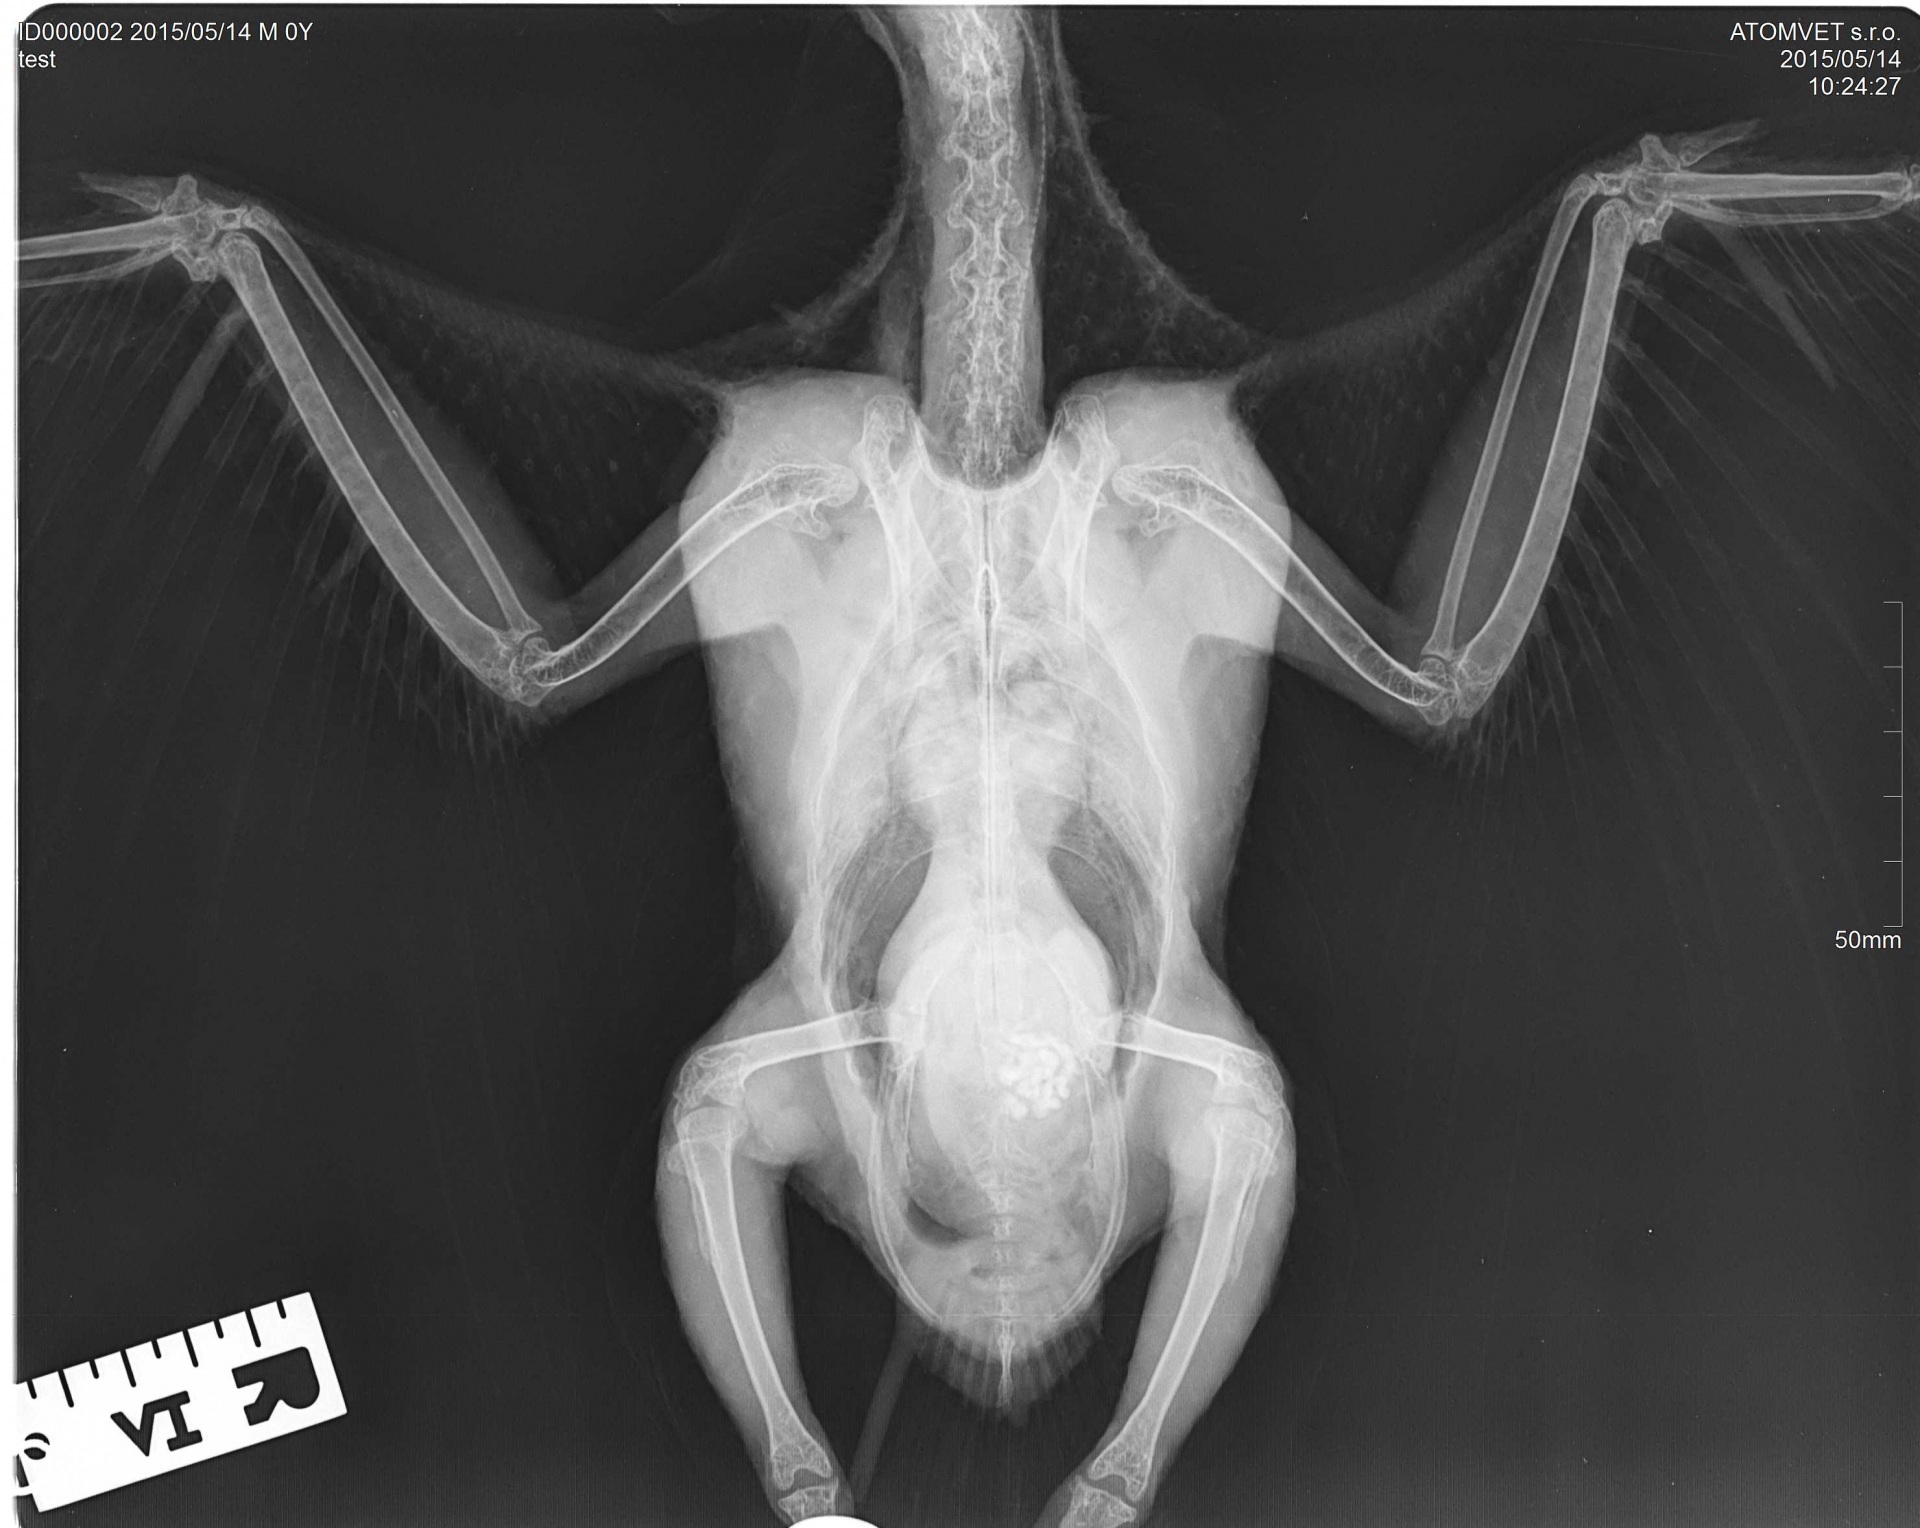

Aviární medicína je koníčkem a zároveň denní rutinou MVDr. Heleny Vaidlové. Naše pracoviště nabízí pomoc kolegům pro referování pacientů a umožňuje hospitalizaci ptáků.

Praxe v zoologické zahradě a úzká spolupráce s manželem Antonínem Vaidlem umožňuje získávat a uplatňovat znalosti a dovednosti i mimo obvyklé hranice nejčastěji ošetřovaných papoušků a dravců. Služby pro majitele ptáků se snažíme neustále rozšiřovat a zlepšovat.